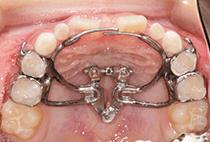

20代女性の患者さま。

八重歯の見た目が気になってご来院されましたが、実は顎の痛みや開口障害など、顎関節症の症状もありました。

そのため、かみ合わせと顎関節症の治療を同時に行ったにもかかわらず、2年間で治療が終了。

かみ合わせが整い咬筋の過緊張も改善しました。咬筋の肥大も治ってフェイスラインがすっきりしました。

最終的には美しい歯並びと、安定した痛みのないかみ合わせが実現しました。

八重歯が気になる

叢生、顎関節症、開口障害

20代女性

矯正治療2年

24回

唇側矯正

矯正:1,161,600円+毎月調整量:6,050円

しっかり前歯を下げるために、インプラントアンカーを使用してコントロールしました。

かみ合わせが整うと咬筋の過緊張が改善。

過緊張による筋肉肥大も改善しフェイスラインもすっきりしました。